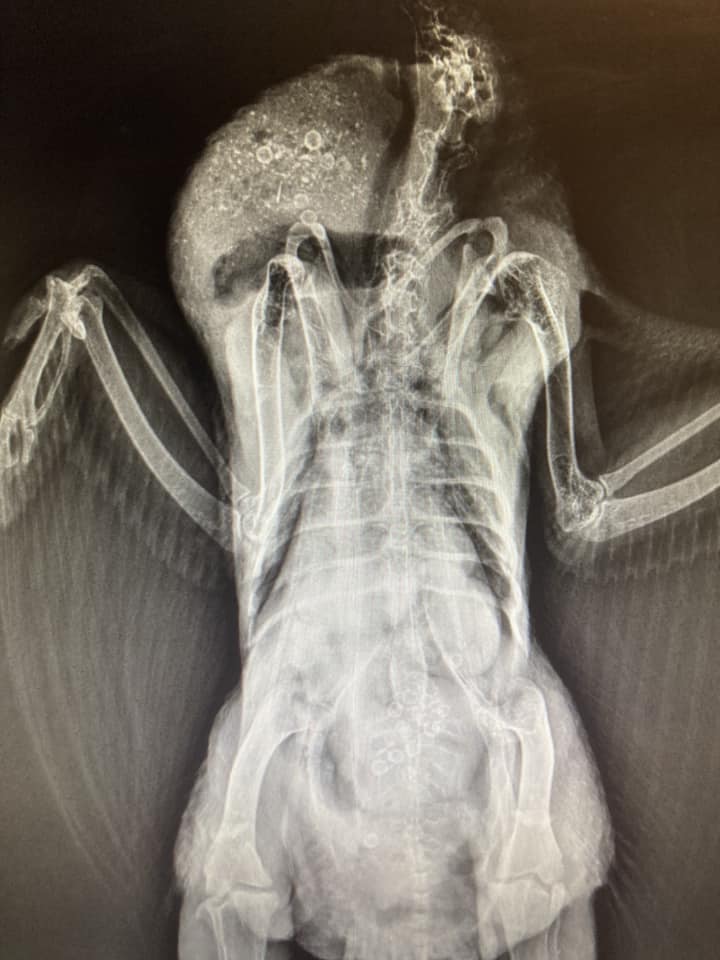

What is going on with my chicken? She presented with a head tilt yesterday and has not laid an egg in a week. She usually lays daily. I took her to work (dog and cat vet) for X-rays. I don’t know what the tiny circles are inside her either. – Kelsey McGuire

Dr Bowes: Judging from the shape and location I think those are cherry pits. They are not dark like lead that would result in neurological issues. I have no explanation for the head tilt.